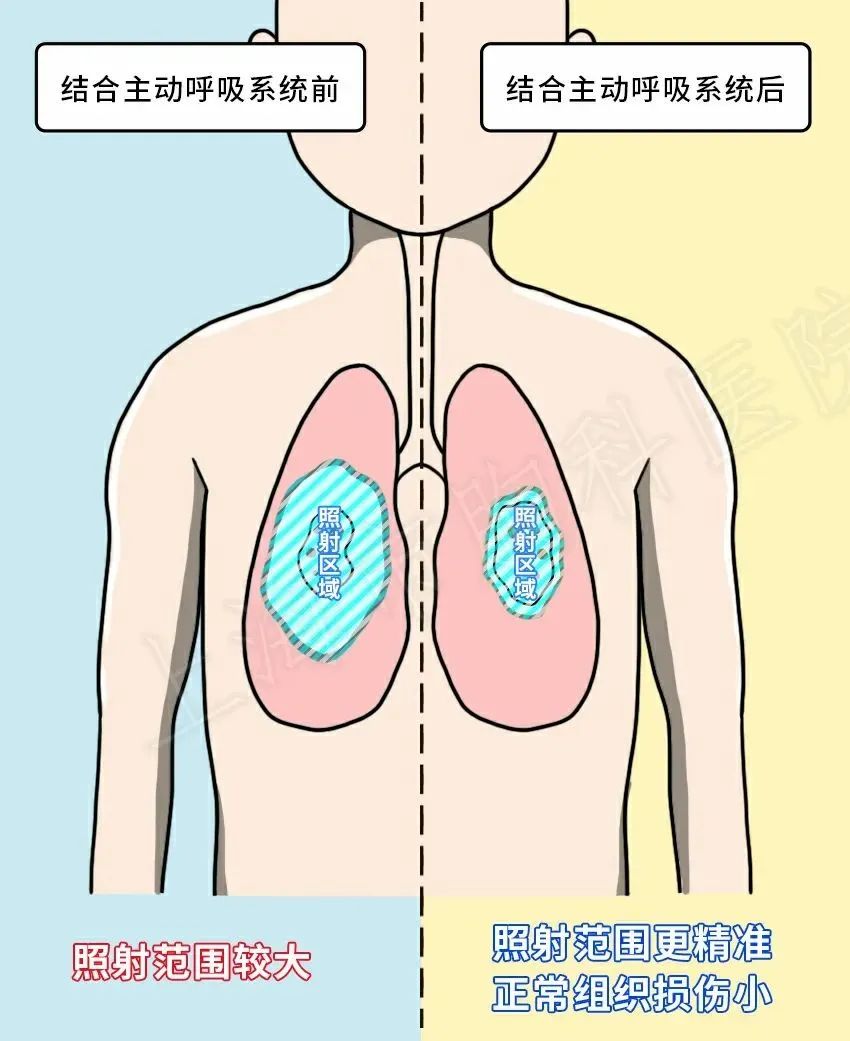

精准放疗的守护者—运动管理技术

精准放疗的守护者—运动管理技术